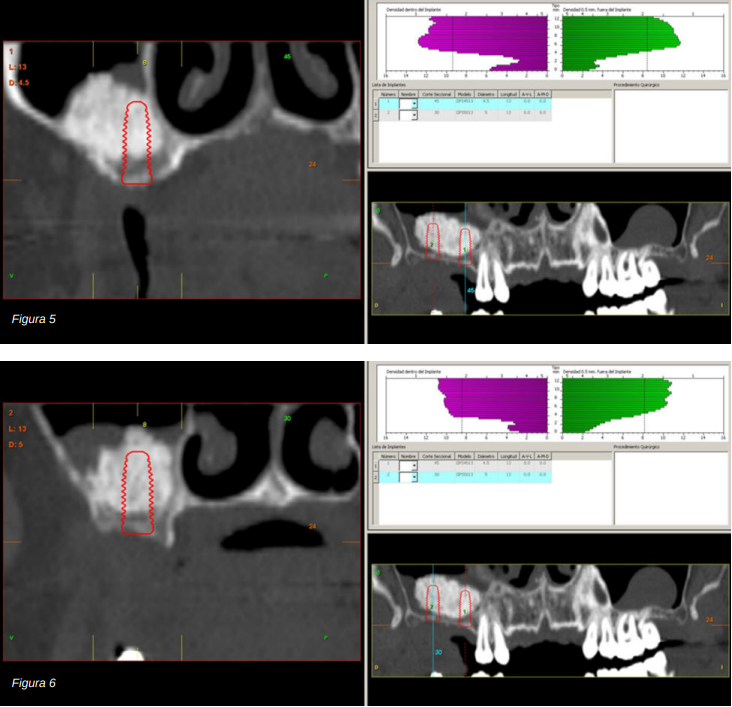

Se realiza la extracción de ambos y la regeneración de los alveolos con PRGF-Endoret para lograr el sellado de la perforación y una evolución lo más favorable posible para la posterior inserción de los implantes en la zona. Tras dos meses podemos observar en el Cone-Beam dental que la perforación se ha cerrado completamente pero el volumen óseo residual en altura para la inserción de los implantes es insuficiente, existiendo únicamente un 2 mm de altura ósea (Figuras 3 y 4).

Por ello, se decide llevar a cabo una elevación de seno utilizando biomaterial (hidroxiapatita bovina) unido a PRGF-Endoret. Se realiza la elevación y tras cinco meses se procede a la evaluación de un nuevo Cone-beam dental para poder visualizar la cantidad y calidad del injerto obtenido para la inserción de los implantes dentales. En los cortes correspondientes a los molares del primer cuadrante podemos observar una perfecta consolidación del injerto con la posibilidad de insertar implantes de 13 mm.

En el año 2007, con los implantes cortos sin pleno desarrollo y sin estudios que demostraran la importancia del diámetro frente a la longitud del implante el protocolo terapéutico para estos casos era muy diferente (Figuras 5-7), centrándose los esfuerzos en la búsqueda de un anclaje por longitud del implante en lugar de buscar la estabilidad bicortical (vestibular-lingual) que realizan los implantes cortos y anchos. Durante este tiempo se produce también